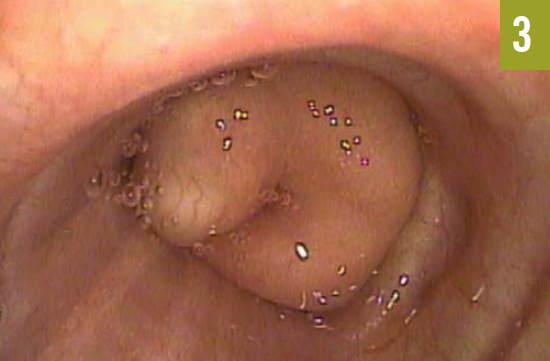

Pulmonary function testing demonstrated a moderate obstructive ventilatory defect with evidence of air trapping. Flexible fiberoptic bronchoscopy discovered a soft, fleshy endobronchial mass causing dynamic and near complete obstruction of the left mainstem bronchus, approximately 3.5 cm distal to the carina (Figure 3). Histopathologic evaluation of the tissue biopsy was consistent with a benign hamartoma.

Figure 3. An endobronchial hamartoma was visualized in the left mainstem bronchus with flexible fiberoptic bronchoscopy.